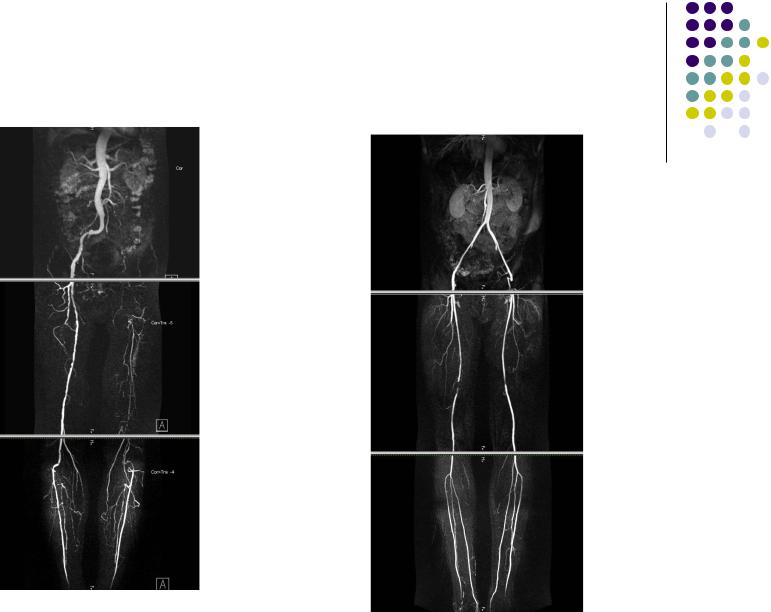

КТангиография

Окклюзия ОПА, НПА, ОБА ,ПБА, ПодА слева Окклюзии ПБА и ВПА

с обеих сторон